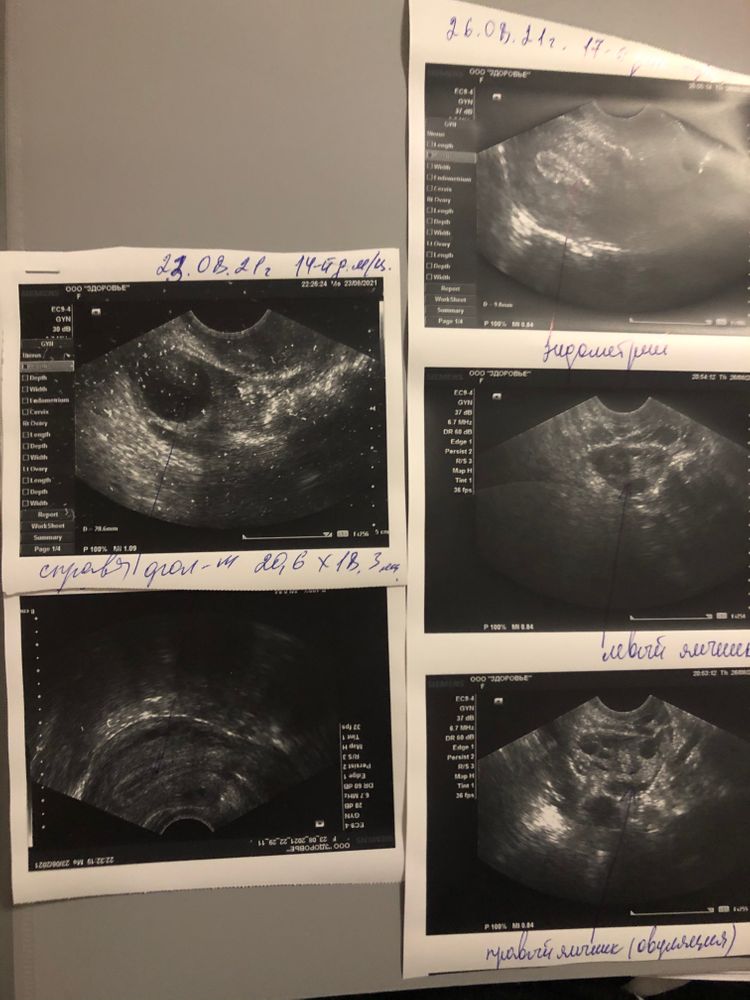

Я вижу большой ДФ - чёткие контуры и чёрный внутри. ЖТ с размытыми контурами и серой взвесью внутри.

Там где написано «левый яичник (овуляция)» и стрелочка к формирующемуся жт. У меня такое же жт было ещё маленькое, когда я приходила в день овуляции. А в правом яичнике у вас ДФ

Tina, предпоследнее фото. Написано, доминантный фолликул 20,6 на 18,3 мм. Он уже мог в тот же день совулировать кстати.

Так вот же, увидела ! 26.08, правый яичник, овуляция!!! Так что считайте ДПО!